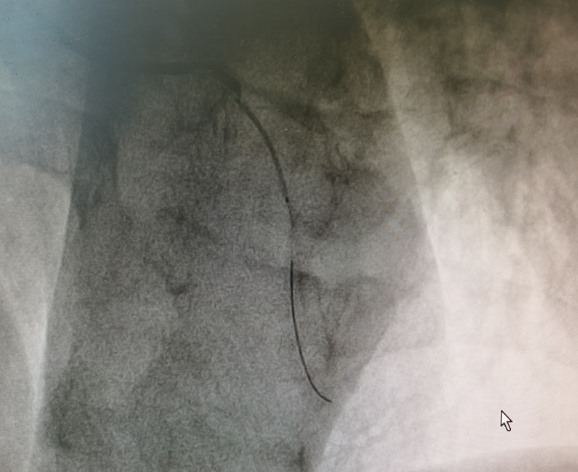

▲患者心血管造影图▲

明确诊断为急性心肌梗死后,立即为患者开通胸痛绿色通道进行抢救,给予患者口服“阿司匹林300mg、阿托伐他汀40mg、替格瑞洛180mg”并静脉注射“普通肝素”抗凝。与家属沟通告知病情,建议立即行冠脉介入手术治疗。患者及家属同意手术后,通过胸痛绿色通道,从我院二马路院区直达文峰院区介入室。冠脉造影术提示前降支血管壁不光整,近段管腔狭窄约60%,高位对角支闭塞;前向血流TIMI0级,于对角支闭塞处植入2.25mm×24mm药物支架1枚,术后收住心血管内科继续住院治疗。从患者到达门诊到行球囊扩张使冠状动脉再灌注治疗时间仅仅为36分钟,实现了生命通道的无缝衔接,使患者得到了高效的救治。目前,患者已顺利康复出院,恢复发病前的工作生活能力。